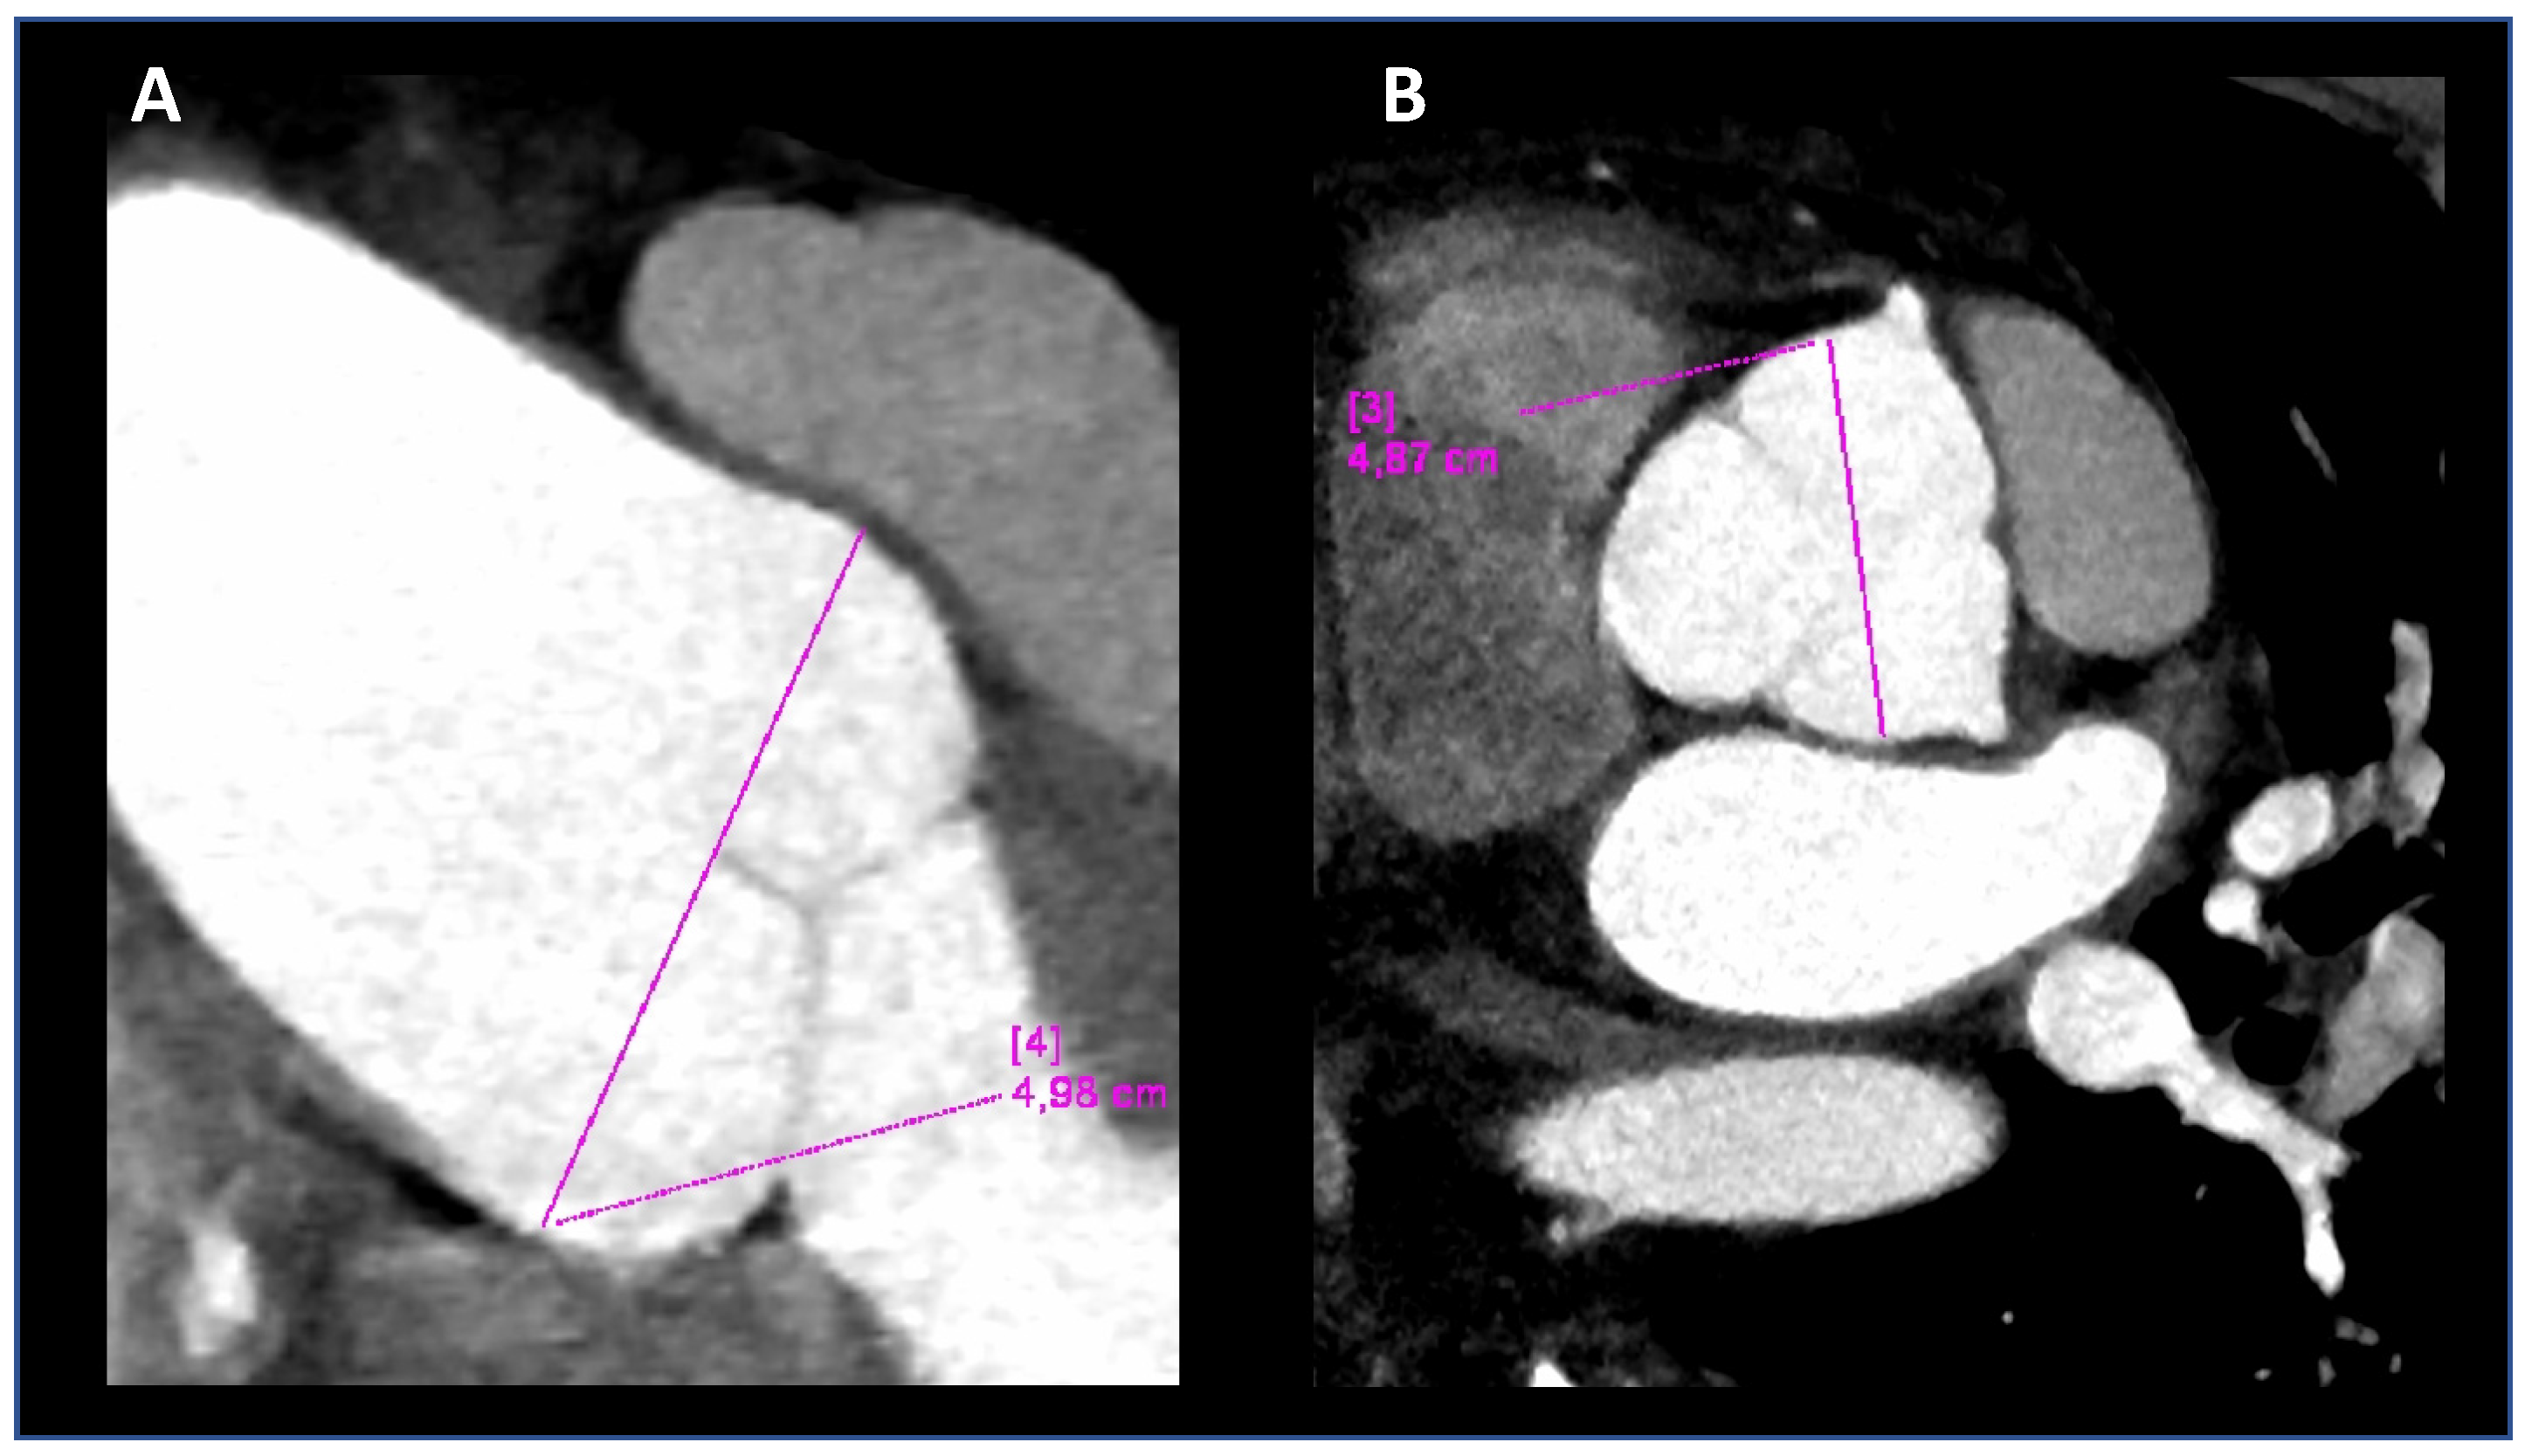

At 40 years old, Computed Tomographic angiography (CTA) of the entire aorta confirmed the ectasia of the aortic root (Figure 2) and revealed mild ectasia of the common left iliac artery (16 × 14 mm) with postostial kinking and tortuosity of the iliac arteries (Figure 2). We have seen both MRI and angio-TC images in 2018 for the first time.

Figure 2. The computed tomographic angiography (CTA) of the thoracic aorta, performed on the propos-itus at 40 years. Coronal oblique (A) and double oblique (B) images, allowing measure-ments in long- and short-axis views, respectively. The aortic root diameters at Valsalva sinuses were 48 and 49 mm.